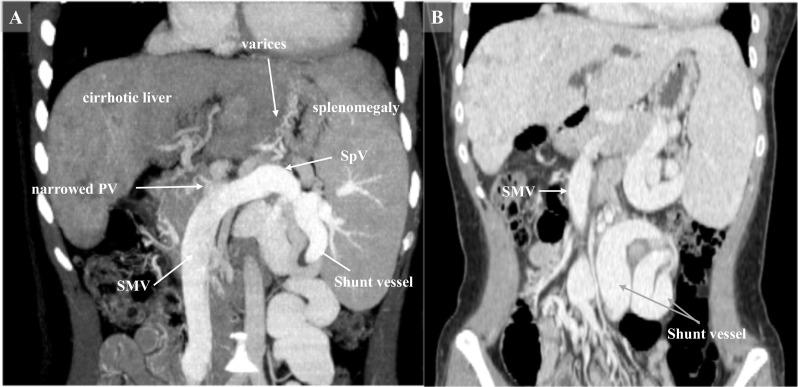

A 25-year-old woman presented with cholestatic liver cirrhosis due to biliary atresia after Kasai procedure. Since her jaundice progressed, she was referred to our hospital for liver transplantation. Laboratory tests showed that her total bilirubin was elevated to 7.6 mg/dL. The Model for End-Stage Liver Disease score was 18, and the Child-Pugh score was 9 (Grade B). She underwent living donor liver transplantation (LDLT) using a right hemi-liver graft procured from her 54-year-old mother. The conventional approach from the cephalad side to the superior mesenteric vein (SMV) and splenic vein (SpV) confluence behind the pancreas was extremely difficult in this case because the confluence of SMV and SpV was close to the lower edge of the pancreas. Therefore, we decided to perform PV reconstruction from the caudal side. The main trunk of PV was documented as narrow (5 mm in diameter), for which retro-pancreatic pull-through PV reconstruction was successfully performed using her own mesosystemic shunt vessel. A contrast computed tomography (CT) scan was performed on postoperative day 5 because of an elevation of D-dimer and found a partial thrombus in the left pulmonary artery, as well as in the PV and left renal vein. Thereafter, thrombolytic therapy with low-molecular-weight heparin was started immediately and switched to a direct oral anticoagulant. The follow-up CT taken 3 months after liver transplantation revealed a patent PV without thrombus; therefore, anticoagulant therapy was discontinued. Currently, the patient has been well and active with a patent PV without anticoagulant therapy for 3 years after LDLT.